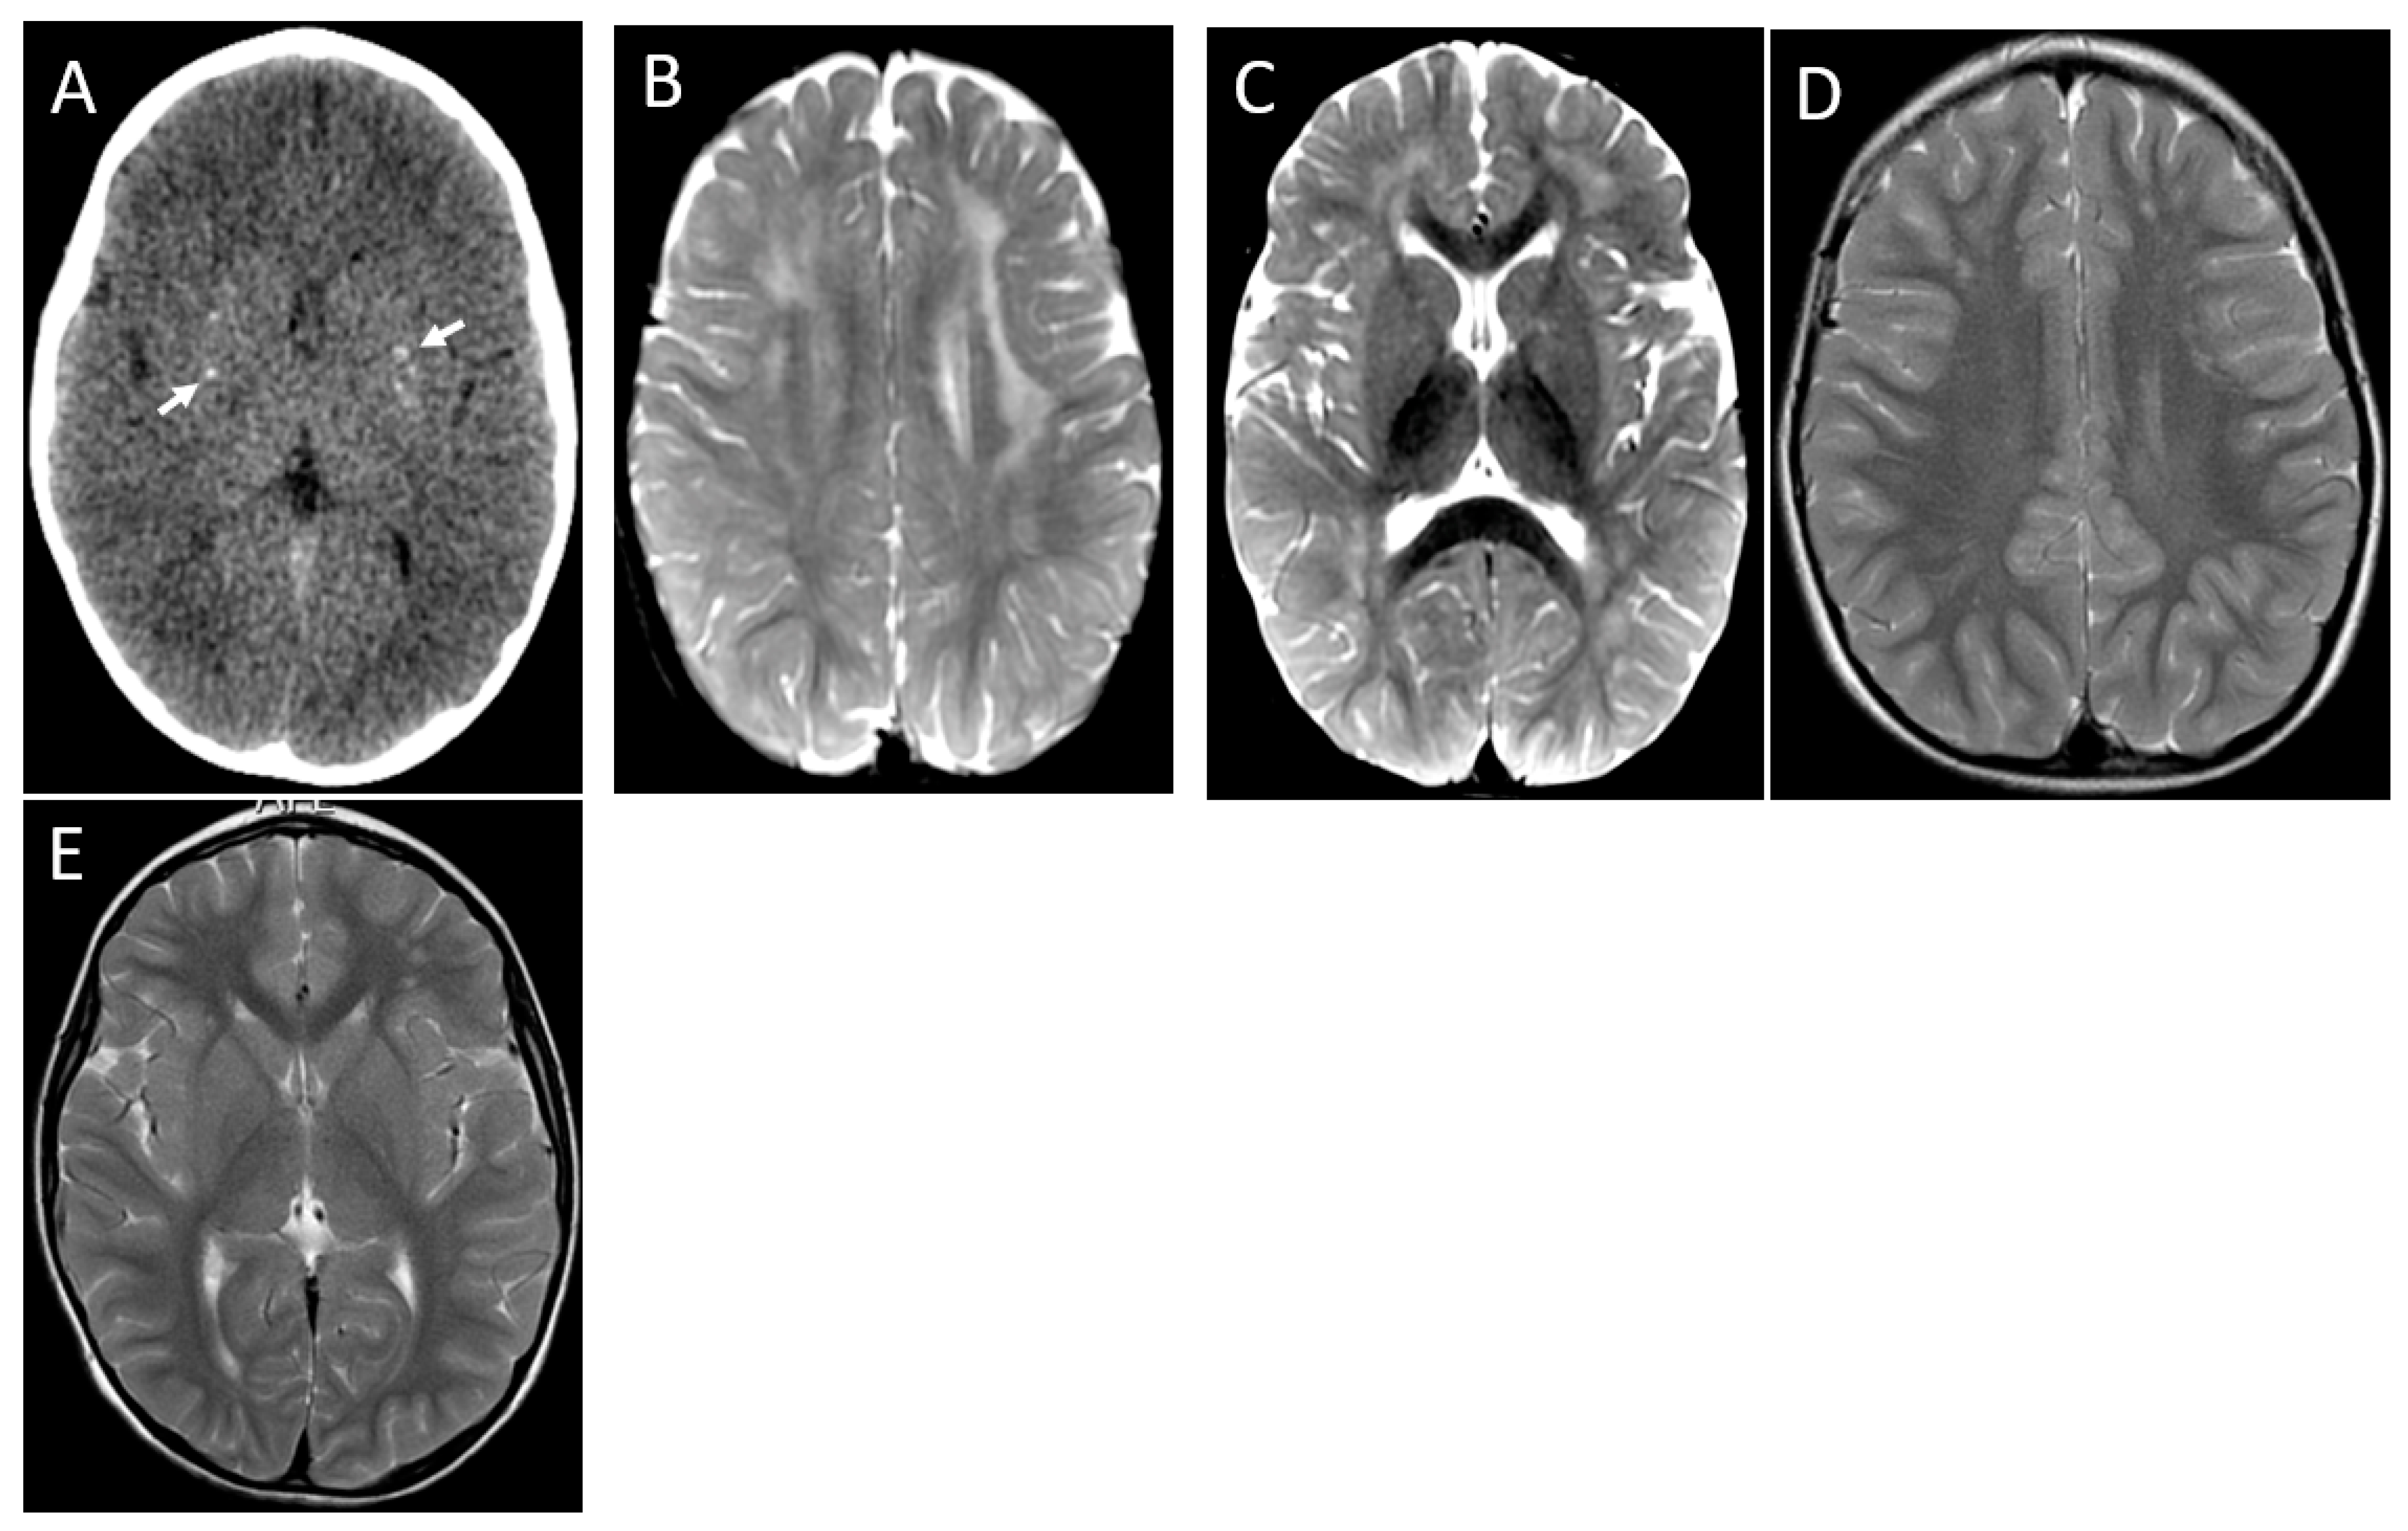

| Image Modality | Patient | 1 | 2 | 3 | 4 | 5 | 6 |

|---|---|---|---|---|---|---|---|

| Distribution | Diffuse/homogeneous | Patchy/asymmetric | Patchy/asymmetric | Patchy/asymmetric | Patchy/asymmetric | Patchy/asymmetric | |

| MRI at onset | Predominant location | Diffuse | Frontal and anterior temporal | Frontal and anterior temporal | Frontal and anterior temporal | Frontal and anterior temporal | Frontal and parietal |

| Infratentorial involvement | Pons | - | - | - | - | Pons | |

| Contrast enhancement | + | - | - | - | - | - | |

| MRI at follow up | Months after onset | 1st episode 8 mo (2 y 3 mo old) | |||||

| 2nd episode | |||||||

| 12 mo | 4 y | 10 mo | 24 mo | 13 y | 5 mo | ||

| (6 years old) | (6 years old) | (2 y 2 mo old) | (3 y 2 mo old) | (13 years old) | (20 mo old) | ||

| WM lesions improvement | Marked | Marked | Marked | Marked | Marked | Marked | |

| Brain Atrophy | Mild | - | Mild | - | - | - | |

| CT scan | Time after onset | 5 y | 4 y | 7 y | 1 mo | 13 y | 2 mo |

| Calcification | - | - | - | Basal ganglia | - | - |